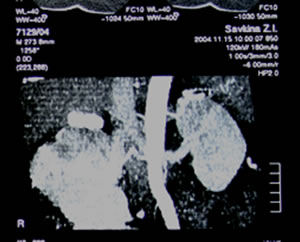

КТ

органов брюшной полости, забрюшинного пространства: |

|